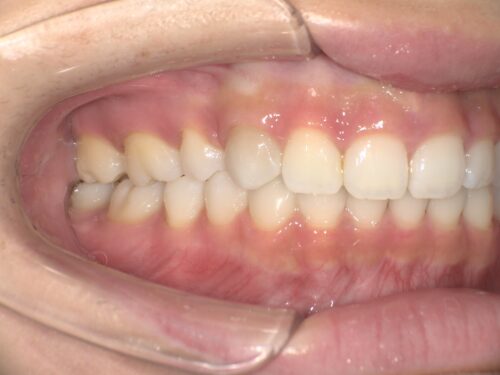

治療後・左側の写真

治療後・右側の写真

横から見ても、上下の前歯の位置関係がしっかり改善されているのが分かります。治療前と比べると、口元の印象がかなり変わりましたね。